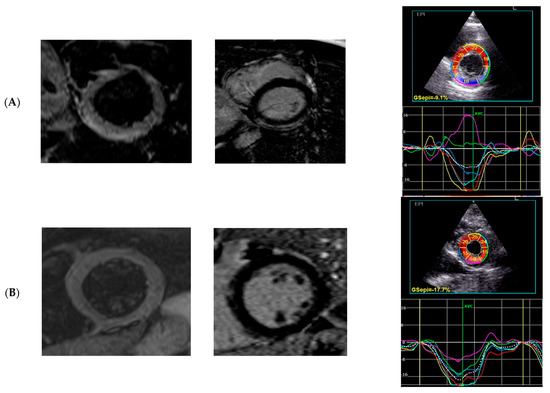

| GLPS Avg, % | −19.1 (−20.4–−16.2) | −17.7 (−20.1–−16.0) | −19.5 (−21.51–−18.5) | 0.074 |

| GCS, % | −17.9 (−20.1–−15.3) | −16.8 (−18.4–−14.5) | −20.0 (−25.3–−17.3) | 0.001 |